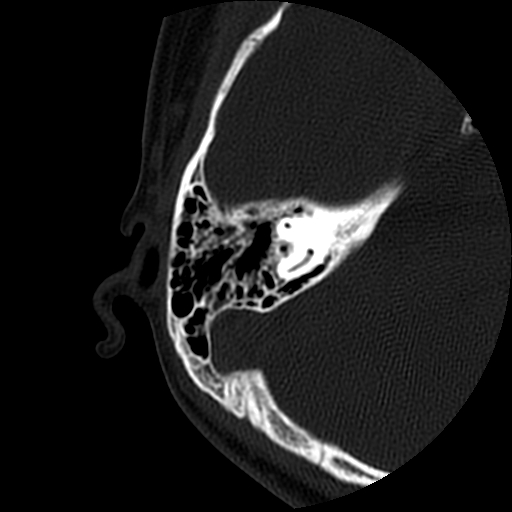

以下是引用随光逐影在2009-8-19 7:25:00的发言:[br]右侧慢性中耳乳突炎,右侧中耳腔及外耳道肉芽肿或胆脂瘤形成。